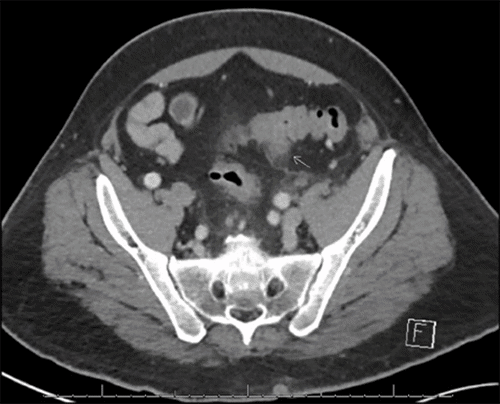

Computed tomography (CT) abdomen/pelvis with contrast demonstrated thrombophlebitis involving at least two branches of the IMV, one of which led to the sigmoid colon (Figure 1A). There was no extension into the portal vein. Mild sigmoid diverticulitis without paracolic abscess or free air was noted. Magnetic resonance imaging (MRI) abdomen/pelvis with contrast demonstrated filling defect of the IMV nearly to its confluence with the splenic vein; rectal wall and perirectal fat inflammation; and subacute sigmoid diverticulitis with lateral tethering to the abdominal wall (Figure 1B). Reactive inflammation of the left ureter and the perinephric region was also visualized.

Figure 1. CT and MRI Scans. Published with Permission

A) CT of resected sigmoid colon segment with diverticulitis (white arrow) and scattered diverticulum